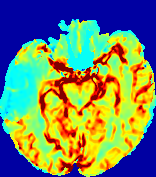

4.3.1 Advection Imaging via Advection-Diffusion

Slice #1Slice #2Slice #3Slice #4Slice #5Slice #6𝐕gt𝟐subscriptnormsuperscript𝐕gt2\|\bf{V}^{\text{gt}}\|_{2}Refer to captionRefer to captionRefer to captionRefer to captionRefer to captionRefer to caption𝐕est𝟐subscriptnormsuperscript𝐕est2\|\bf{V}^{\text{est}}\|_{2}Refer to captionRefer to captionRefer to captionRefer to captionRefer to captionRefer to captionRefer to caption1.51.51.51.21.21.20.90.90.90.60.60.60.30.30.30.00.00.0(mm/s)𝑚𝑚𝑠(mm/s)Destsuperscript𝐷estD^{\text{est}}Refer to captionRefer to captionRefer to captionRefer to captionRefer to captionRefer to captionRefer to caption0.0150.0150.0150.0120.0120.0120.0090.0090.0090.0060.0060.0060.0030.0030.0030.0000.0000.000(mm2/s)𝑚superscript𝑚2𝑠(mm^{2}/s)

Figure 14: PIANO identifiability testing: advection imaging via advection-diffusion. Top row shows 𝐕gt2subscriptnormsuperscript𝐕gt2\|{\bf{V}}^{\text{gt}}\|_{2} used for simulating ground truth pure advection. Rows below show the estimated 𝐕est2subscriptnormsuperscript𝐕est2\|{\bf{V}}^{\text{est}}\|_{2} and Destsuperscript𝐷estD^{\text{est}} on corresponding slices. Note that the plotted value scale for Destsuperscript𝐷estD^{\text{est}} is 0.01 of that for 𝐕gt2subscriptnormsuperscript𝐕gt2\|{\bf{V}}^{\text{gt}}\|_{2} and 𝐕est2subscriptnormsuperscript𝐕est2\|{\bf{V}}^{\text{est}}\|_{2}.

We use the same ‘Advection Imaging’ simulation of Sec. 4.2.1 as the concentration dataset for PIANO. However, instead of modeling pure advection (Eq. 15), we let PIANO estimate both velocity 𝐕estsuperscript𝐕est{\bf{V}}^{\text{est}} and diffusivity Destsuperscript𝐷estD^{\text{est}} via the advection-diffusion PDE (Eq. 2) underlying the proposed PIANO model. Fig. 14 shows the estimated 𝐕est2,subscriptnormsuperscript𝐕est2\|{\bf{V}}^{\text{est}}\|_{2}, and Destsuperscript𝐷estD^{\text{est}} fields for one patient. Although PIANO has the freedom to estimate both a velocity and a diffusivity field from pure advection, PIANO differentiates well between advection and diffusion: the estimated 𝐕est2subscriptnormsuperscript𝐕est2\|{\bf{V}}^{\text{est}}\|_{2} successfully reproduces the ground truth 𝐕gt2subscriptnormsuperscript𝐕gt2\|{\bf{V}}^{\text{gt}}\|_{2} governing the simulated advection process, just as it already did in the ‘Advection Imaging via Advection’ test (Fig. 12). More importantly, the estimated diffusivity Destsuperscript𝐷estD^{\text{est}} is orders of magnitudes smaller than 𝐕est2subscriptnormsuperscript𝐕est2\|{\bf{V}}^{\text{est}}\|_{2}, indicating the estimated diffusion is negligible compared to the estimated advection, which is highly consistent with the underlying pure advection of the simulated data.